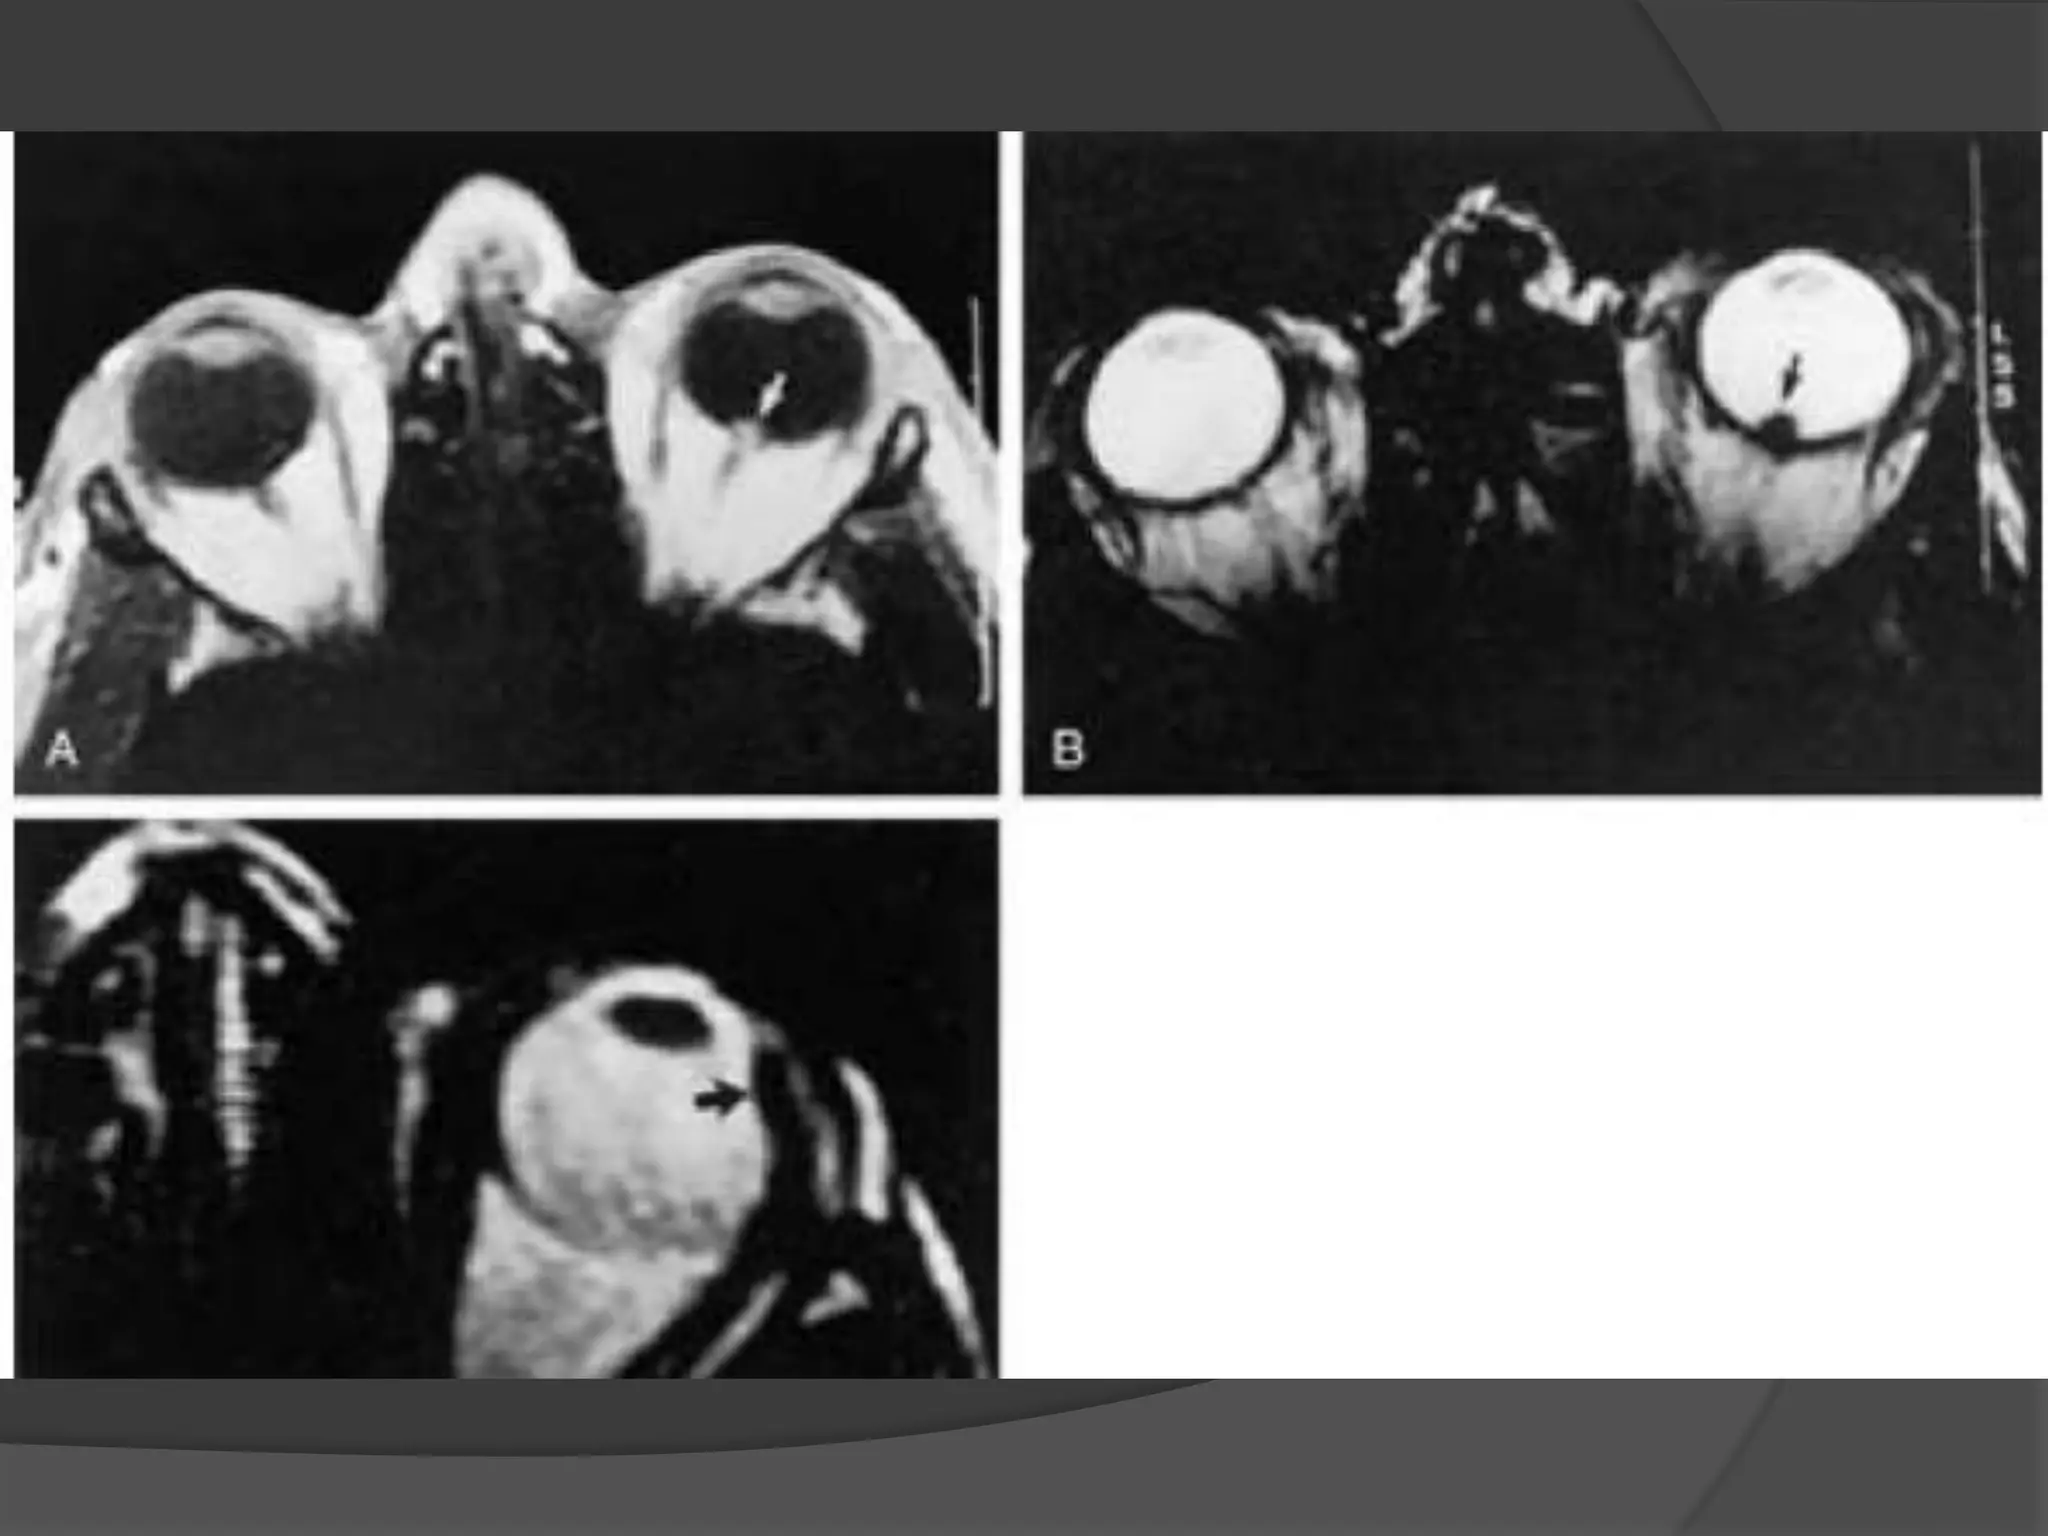

Fig A. Scleral pseudotumour. Marked thickening and irregularity of

the sclera of the right globe involves the adjacent retro-orbital fat.

Fig B. Diffuse pseudotumour. Axial MR T1WI showing a diffuse mass

in the right orbit due to pseudotumour.

Fig A. Scleralpseudotumour. Marked thickening and irregularity of the sclera of the right globe involves the adjacent retro-orbital fat. Fig B. Diffuse pseudotumour. Axial MR T1WI showing a diffuse mass in the right orbit due to pseudotumour.